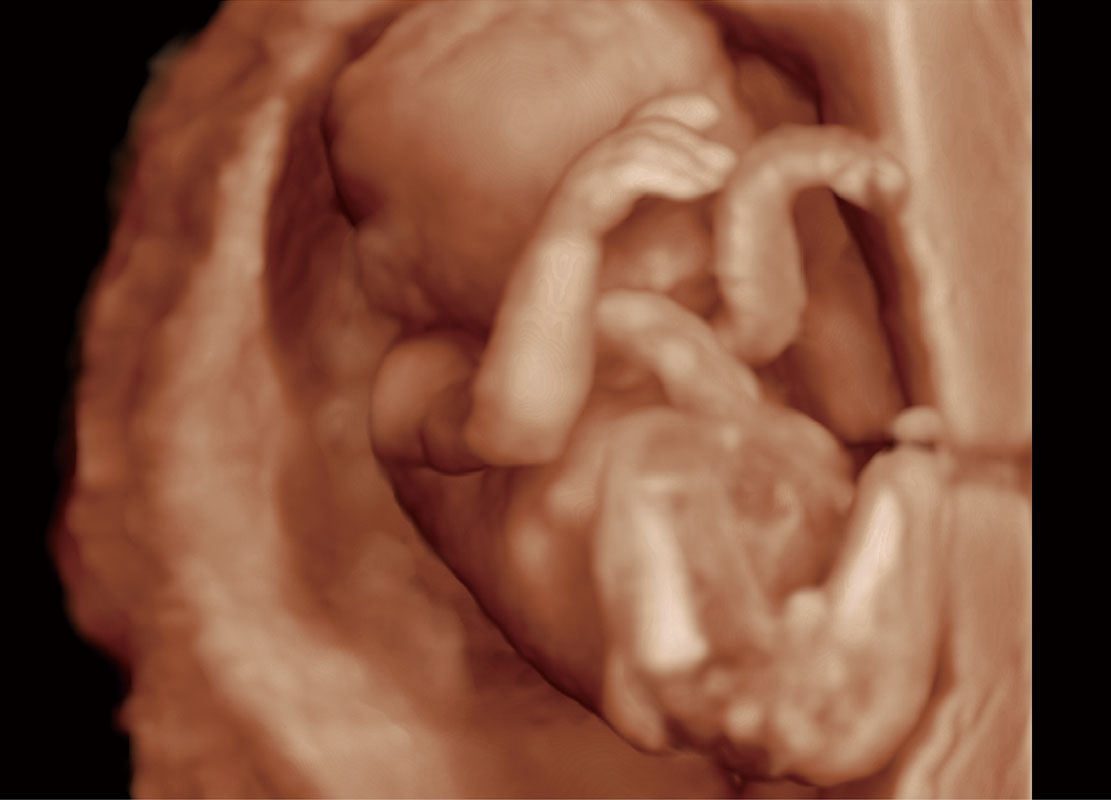

腔内三维-光影成像

高分辨率容积成像-早孕胎儿

P60提供简单易学易用的高端诊断工具,为您中晚孕筛查提供快速清晰的解剖信息。

S-Fetus能够助您在实时扫查过程中自动识别标准切面、自动测量并录入报告。一个按键,即可快速、高效地获取胎儿生理指标,简化您的产科检查操作。